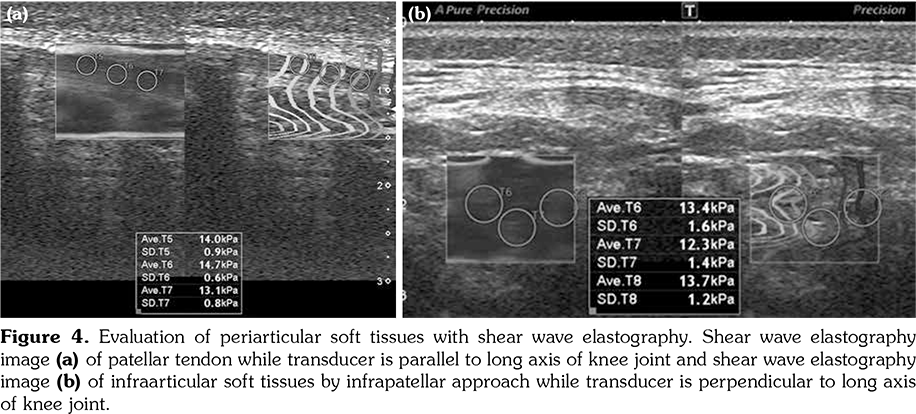

All patients and healthy volunteers were screened with Canon Aplio 500 Platinum US device (Canon Medical Systems, Tokyo, Japan) equipped with SMI, PD and SWE functions. All participants were examined in supine position and their knees were in extension (Figures 1, 2). Once the gray scale US examination confirmed the arthritis based on synovial thickening, joint effusion and periarticular echogenicity, then SMI and SWE were performed to the supraarticular and infraarticular soft tissues concerning the synovium and periarticular soft tissues. VI is a novel parameter determined for SMI and PD corresponding the ratio of colored pixels to the total pixels within the selected region of interest (ROI). VI was calculated automatically on colored SMI and PD images over the selected rectangular shaped ROI with edges measured 5x15 mm (Figure 3). Mean VI values were calculated by averaging results of three different acquisitions of PD and SMI. The ROI was placed perpendicular to the long axis of the knee joint at the supraarticular and infraarticular locations including the synovium and periarticular soft tissues. On SWE evaluation, the QT and PT were demonstrated along with their long axis. Three different ROIs for SWE were performed from the tendon halves closer to the knee joints. Each ROI was in circle shape and 3 mm in diameter. We depicted mean elasticity for PT, QT, supraarticular soft tissues (SAST) and infraarticular soft tissues (IAST) (Figures 4, 5).

The mean SWE values obtained from SAST including synovium and suprapatellar fat pad was 10.7±2.5 kPa in study group and 9.9±2.3 kPa in the control group (p>0.05). The mean SWE values obtained from IAST including synovium and infraarticular fat pad was 9.8±2.4 kPa in study group and 9.4±2.3 kPa in the control group (p>0.05). No significant difference was found among SWE values of periarticular soft tissues among study and control subjects. The mean SWE of PT was 19.7±6.9 kPa in the study group and 16.5±4.8 kPa in the control group. Although the mean QT SWE (19±6.1 kPa) was higher in the study group than the control group (15.7±4.8 kPa), the differences among the mean SWE values of QT and PT failed to reach statistically significant levels (p>0.05) (Table 1).